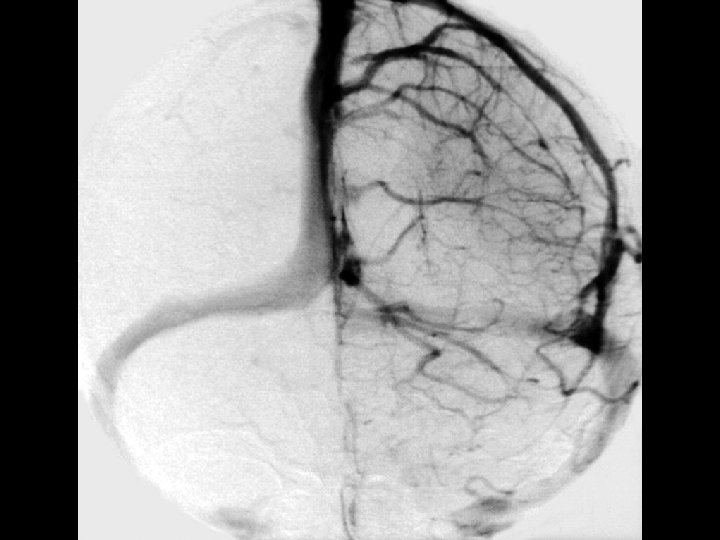

Angiographic digression to aid the understanding of venous angiography Michigan Neurosurgery

Early Venous phase Michigan Neurosurgery